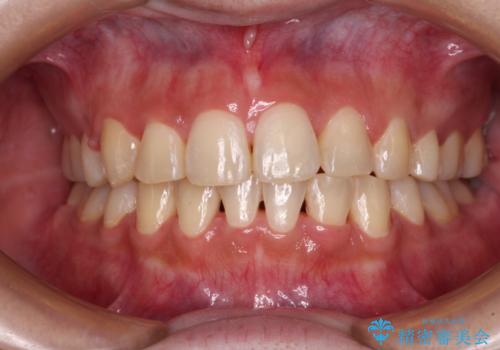

前歯の突出を軽減 インビザラインによる抜歯矯正

- 上の前歯の捻じれと突出感を気にして来院された患者様です。

目立たない装置を希望とのことで、上顎左右第一小臼歯を抜歯し、インビザラインにて矯正治療を行うこととしました。